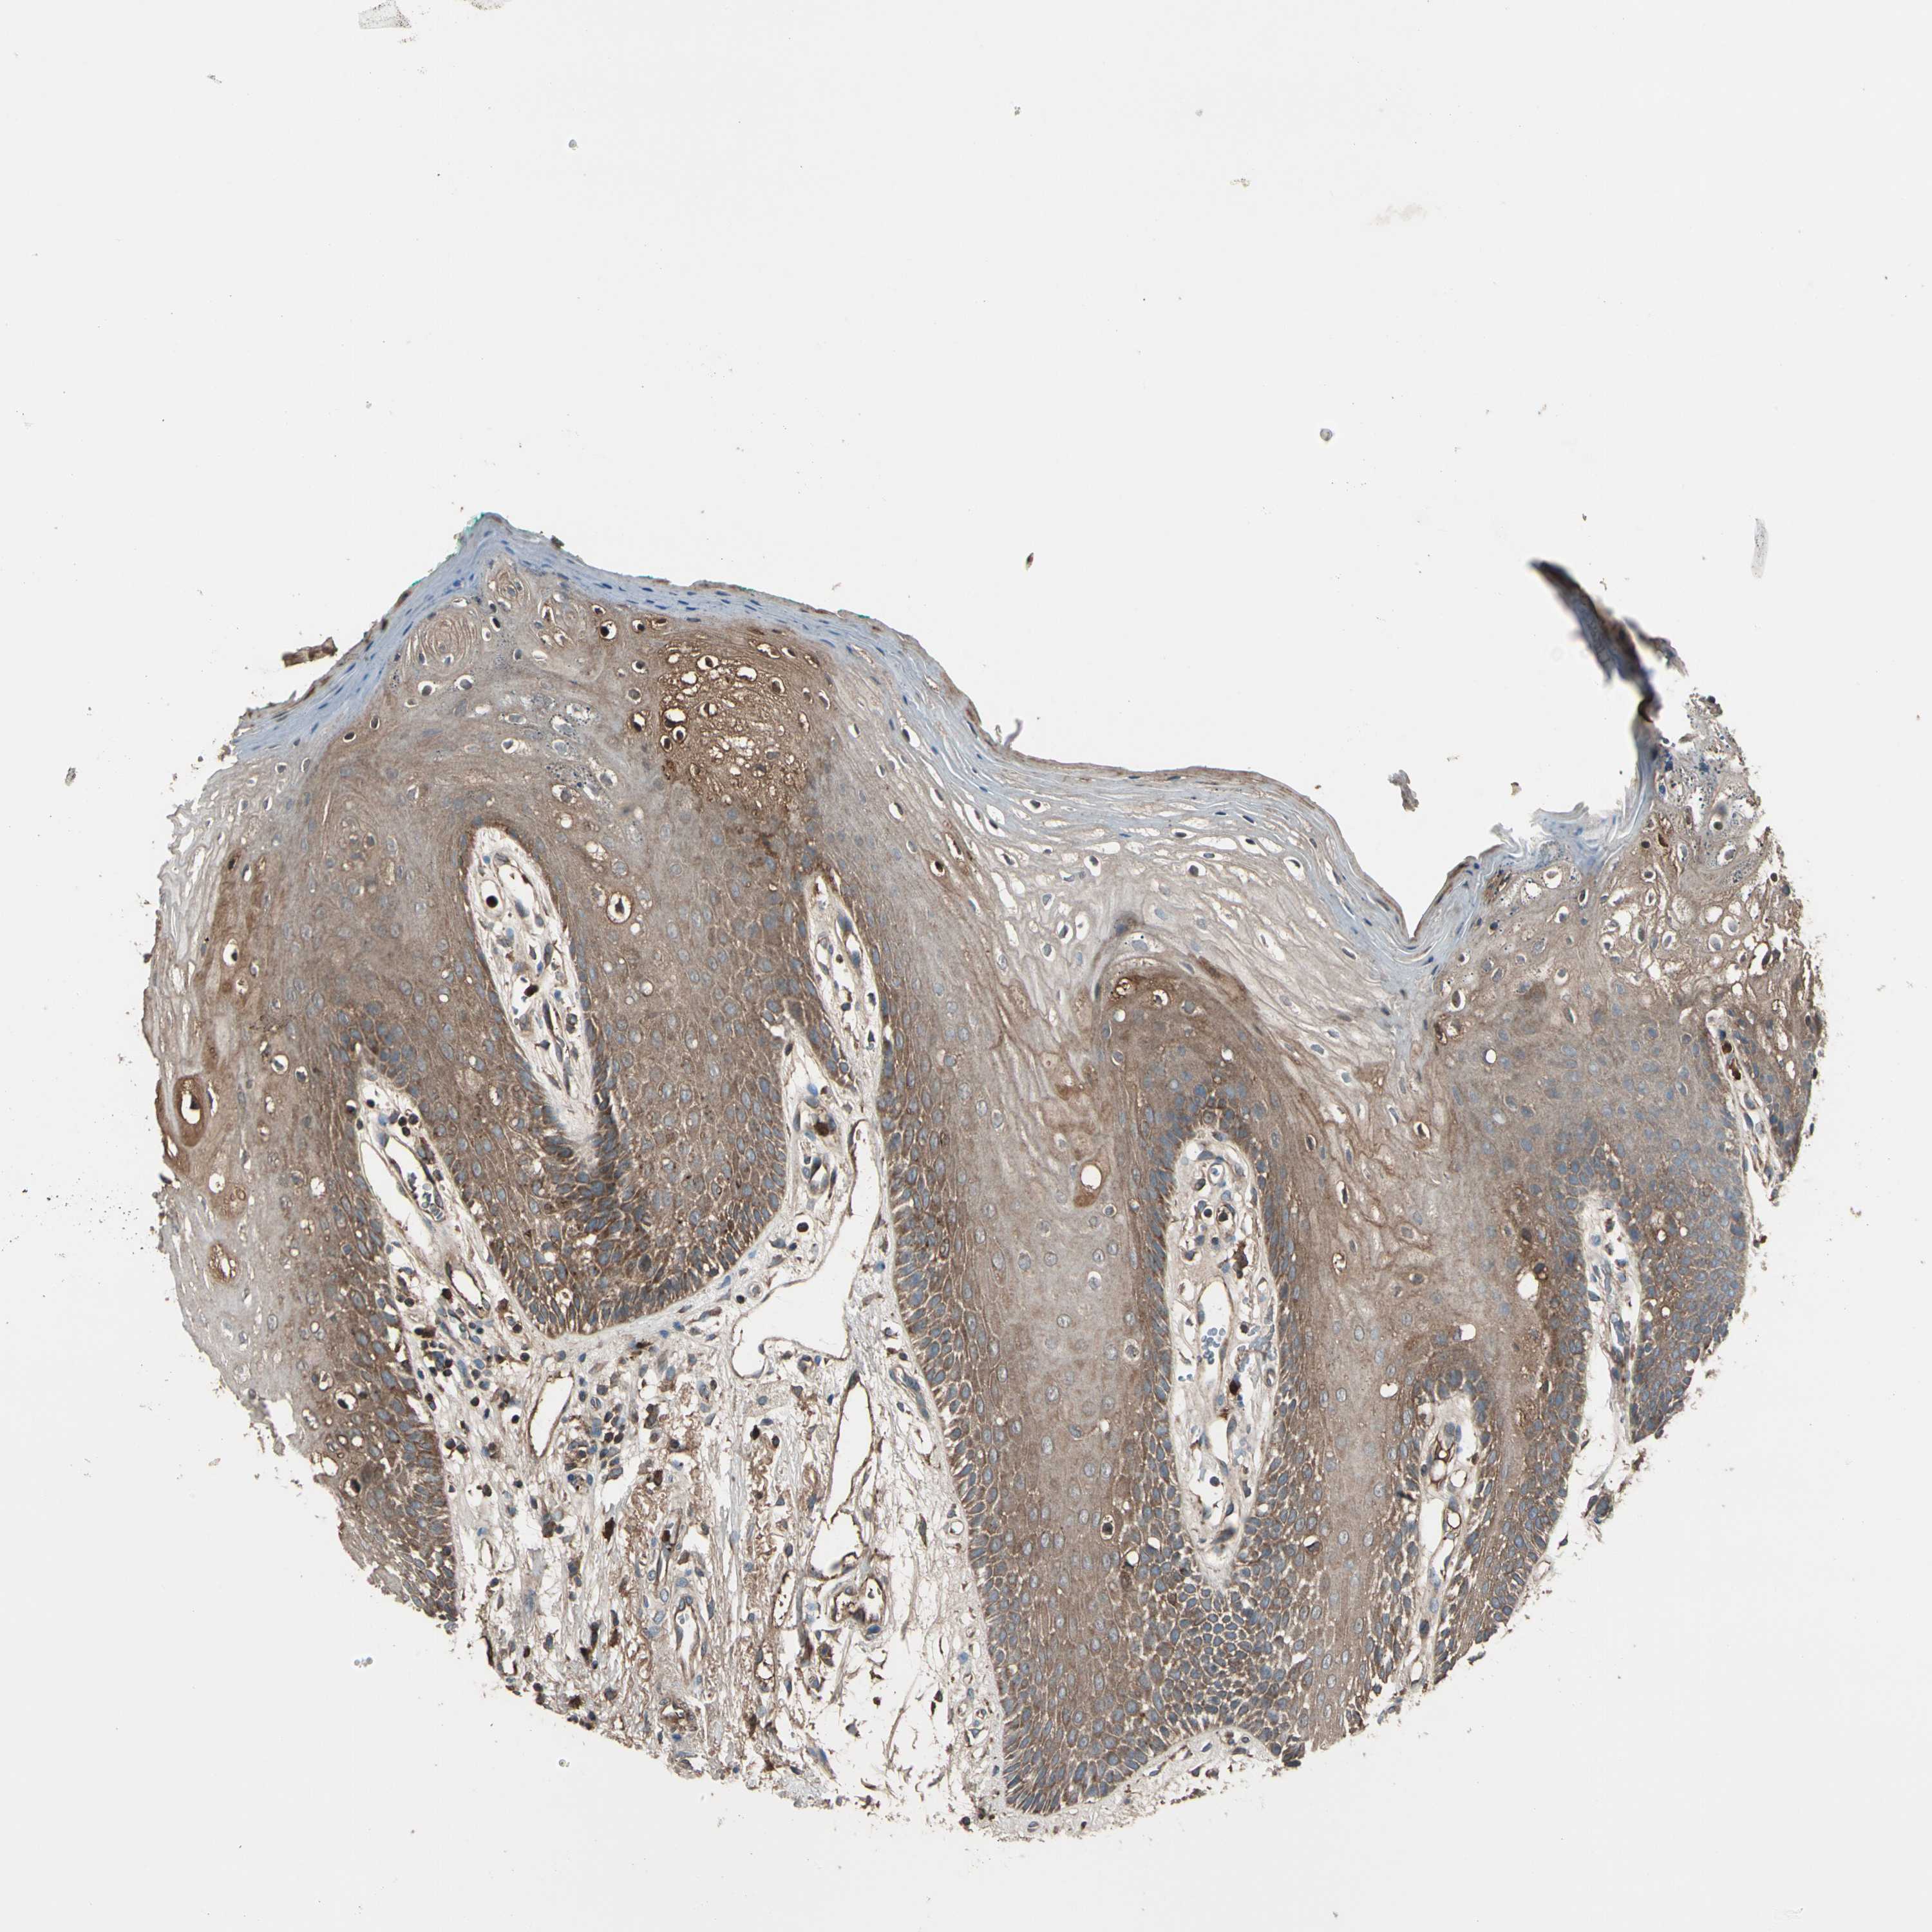

STX11